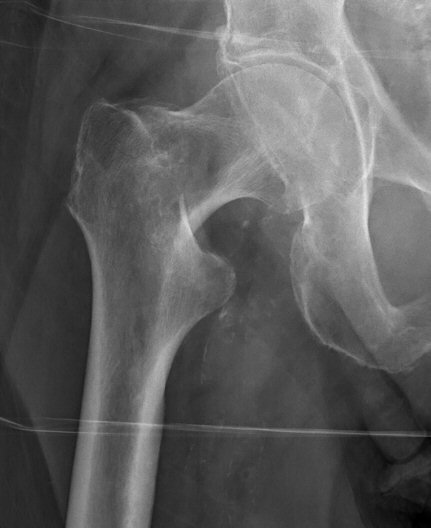

- Cervikal, fraktur av kollum femoris. Klassificeras enligt Garden som bedöms på frontalbild. Det finns något olika tolkningar av denna klassifikation. Ofta används istället "Garden 1-2" för odislocerad eller måttligt dislocerad fraktur och "Garden 3-4" för mer dislocerad.

- Garden 1: inkomplett fraktur med intakt inferior kant, kan vara valgusställd [1]

- Garden 2: genomgående fraktur utan annan felställning än kompression [1]

- Garden 3: genomgående fraktur med kontakt inferiort, varusställd [1]

- Garden 4: genomgående fraktur, parallellförskjuten, kaput ligger rätt i acetabulum [1]